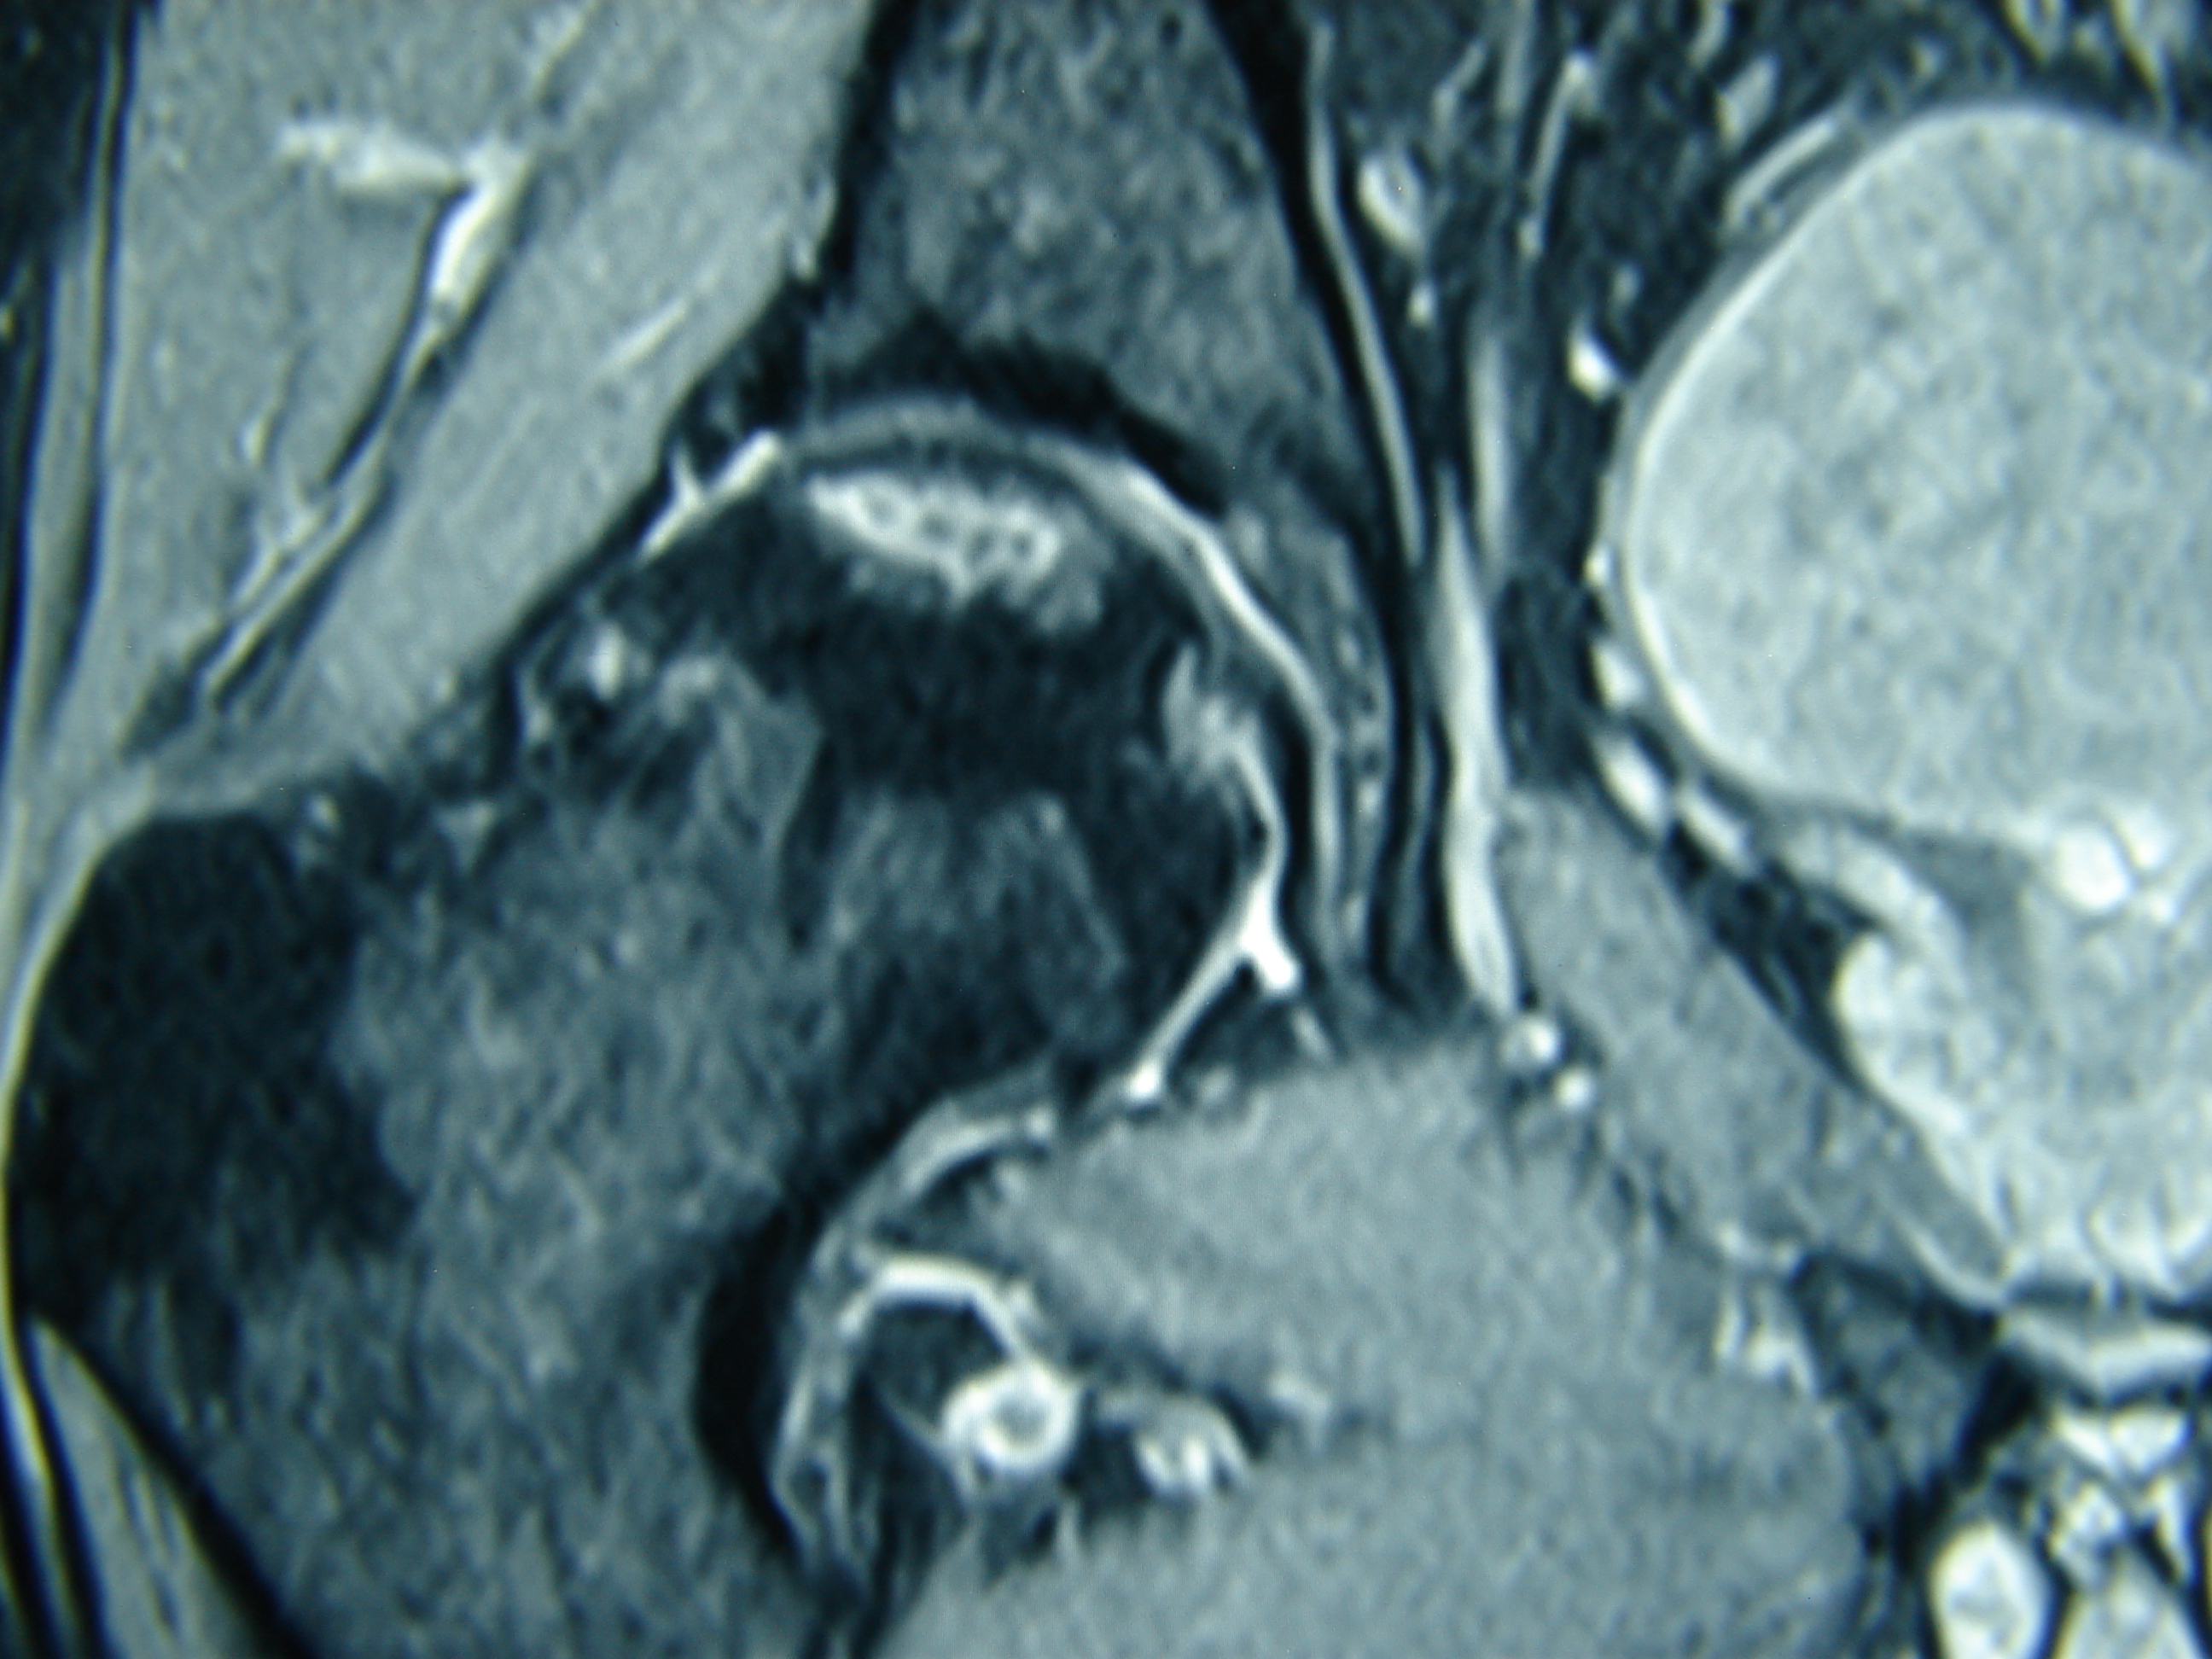

Εικόνα 4: Μετεγχειρητική μαγνητική τομογραφία έξι μήνες μετά τη χειρουργική επέμβαση

Παρατηρούνται α) Ακεραιότητα της αρθρικής επιφανείας της μηριαίας κεφαλής β) Σωστή θέση του ήλου εντός της μηριαίας κεφαλής